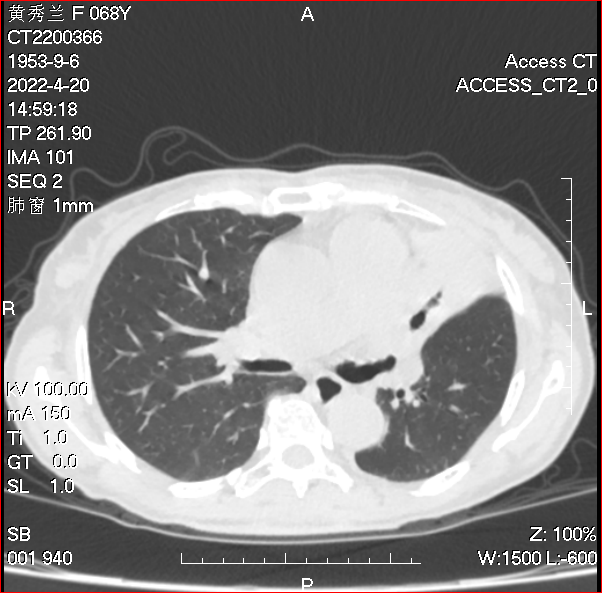

【咳嗽、气促及顽固的“肉芽”均消失不见】黄女士在我所结核病控制科门诊继续抗结核治疗1月,咳嗽、气促症状消失了。至2022年4月20日复查胸部CT“左上肺肺不张较前好转、左主支气管狭窄减轻”(图九、图十、图十一),复查支气管镜“左上叶支气管开口见一肉芽较前明显缩小”(图十二),再次行支气管镜介导腔内冷冻治疗,肉芽融解消失(图十三)。

图九

图十

图十一